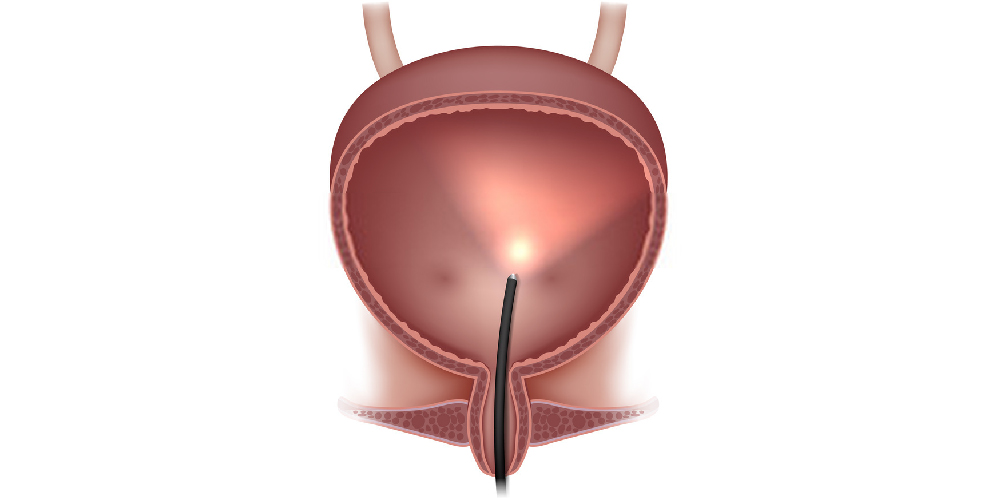

BPH Treatments | Grimaldi Center | Dr. Grimaldi | Chula ...

BPH Treatments | Grimaldi Center | Dr. Grimaldi | Chula ... from grimaldicenter.com